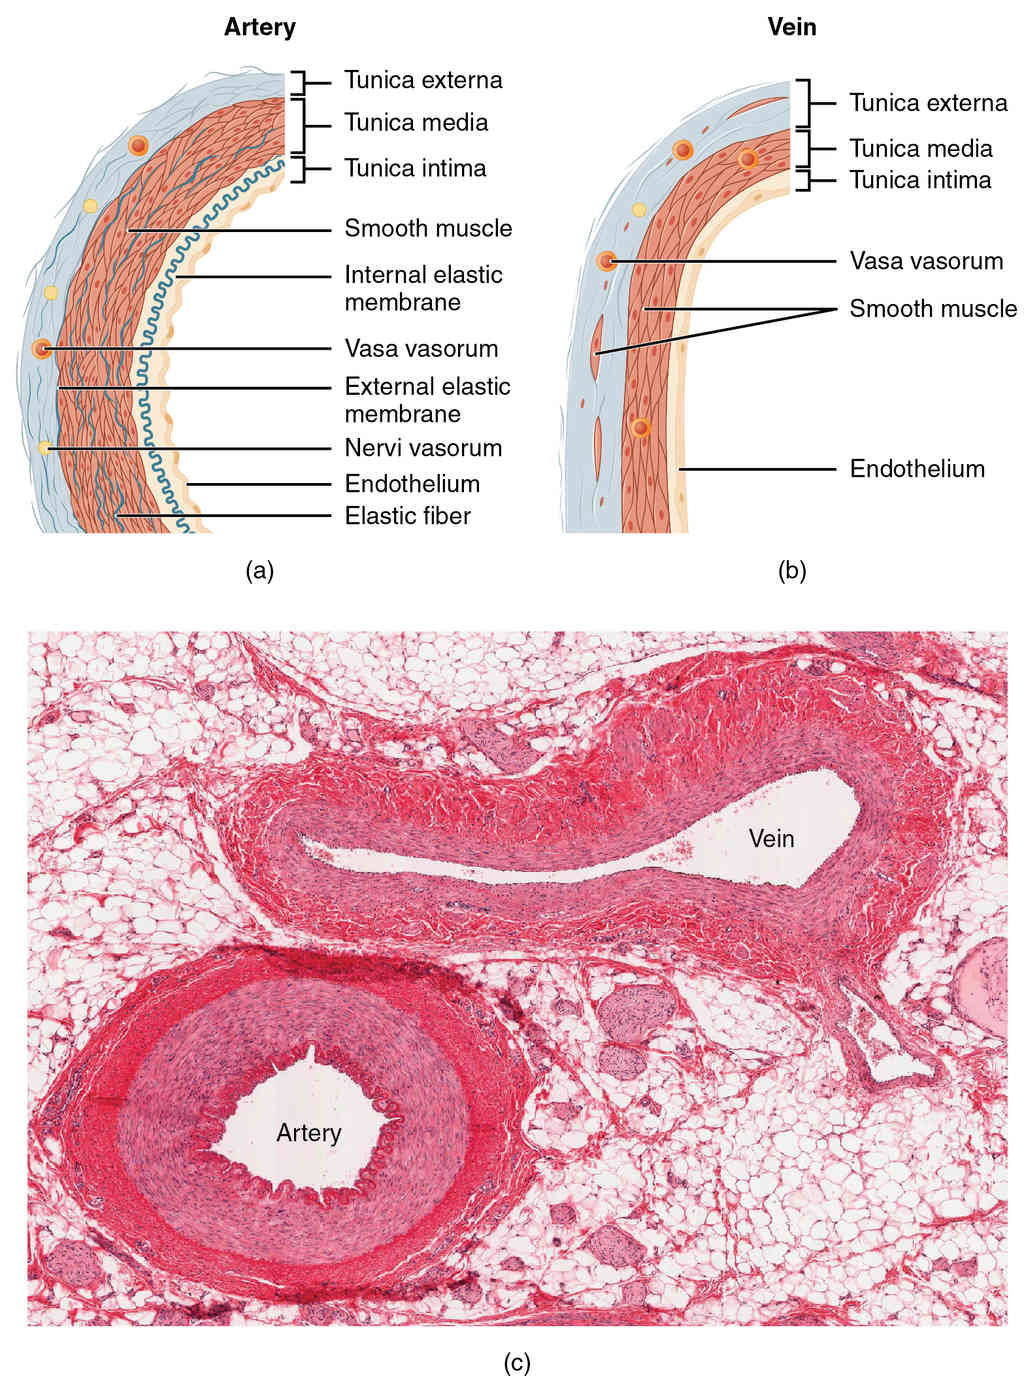

This page is under construction. For now, it is just a resource of the images found in the OpenStax Anatomy and Physiology Handbook. It wil slowly change into a revision tool. Each slide has a number. Use this to refer to the slide. When completed, it will have an unlabelled section, with labelled slides in parallel. On the unlabelled slides, write your answer and use the labelled slide to assess yourself. Keep track by also noting the number on each slide. Improvement at each attempt is important, more so than full marks on a first attempt.